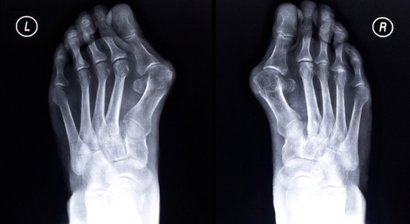

Fußchirurgie

Als Facharzt für Orthopädie und orthopädische Chirurgie setze ich bei meinen Patienten primär auf konservative Therapien - getreu der Philosophie "Schmerzfrei ohne Spritzen" setze ich alles daran, um meinen Patienten im Rahmen einer individuellen und bedürfnisorientierten Th...